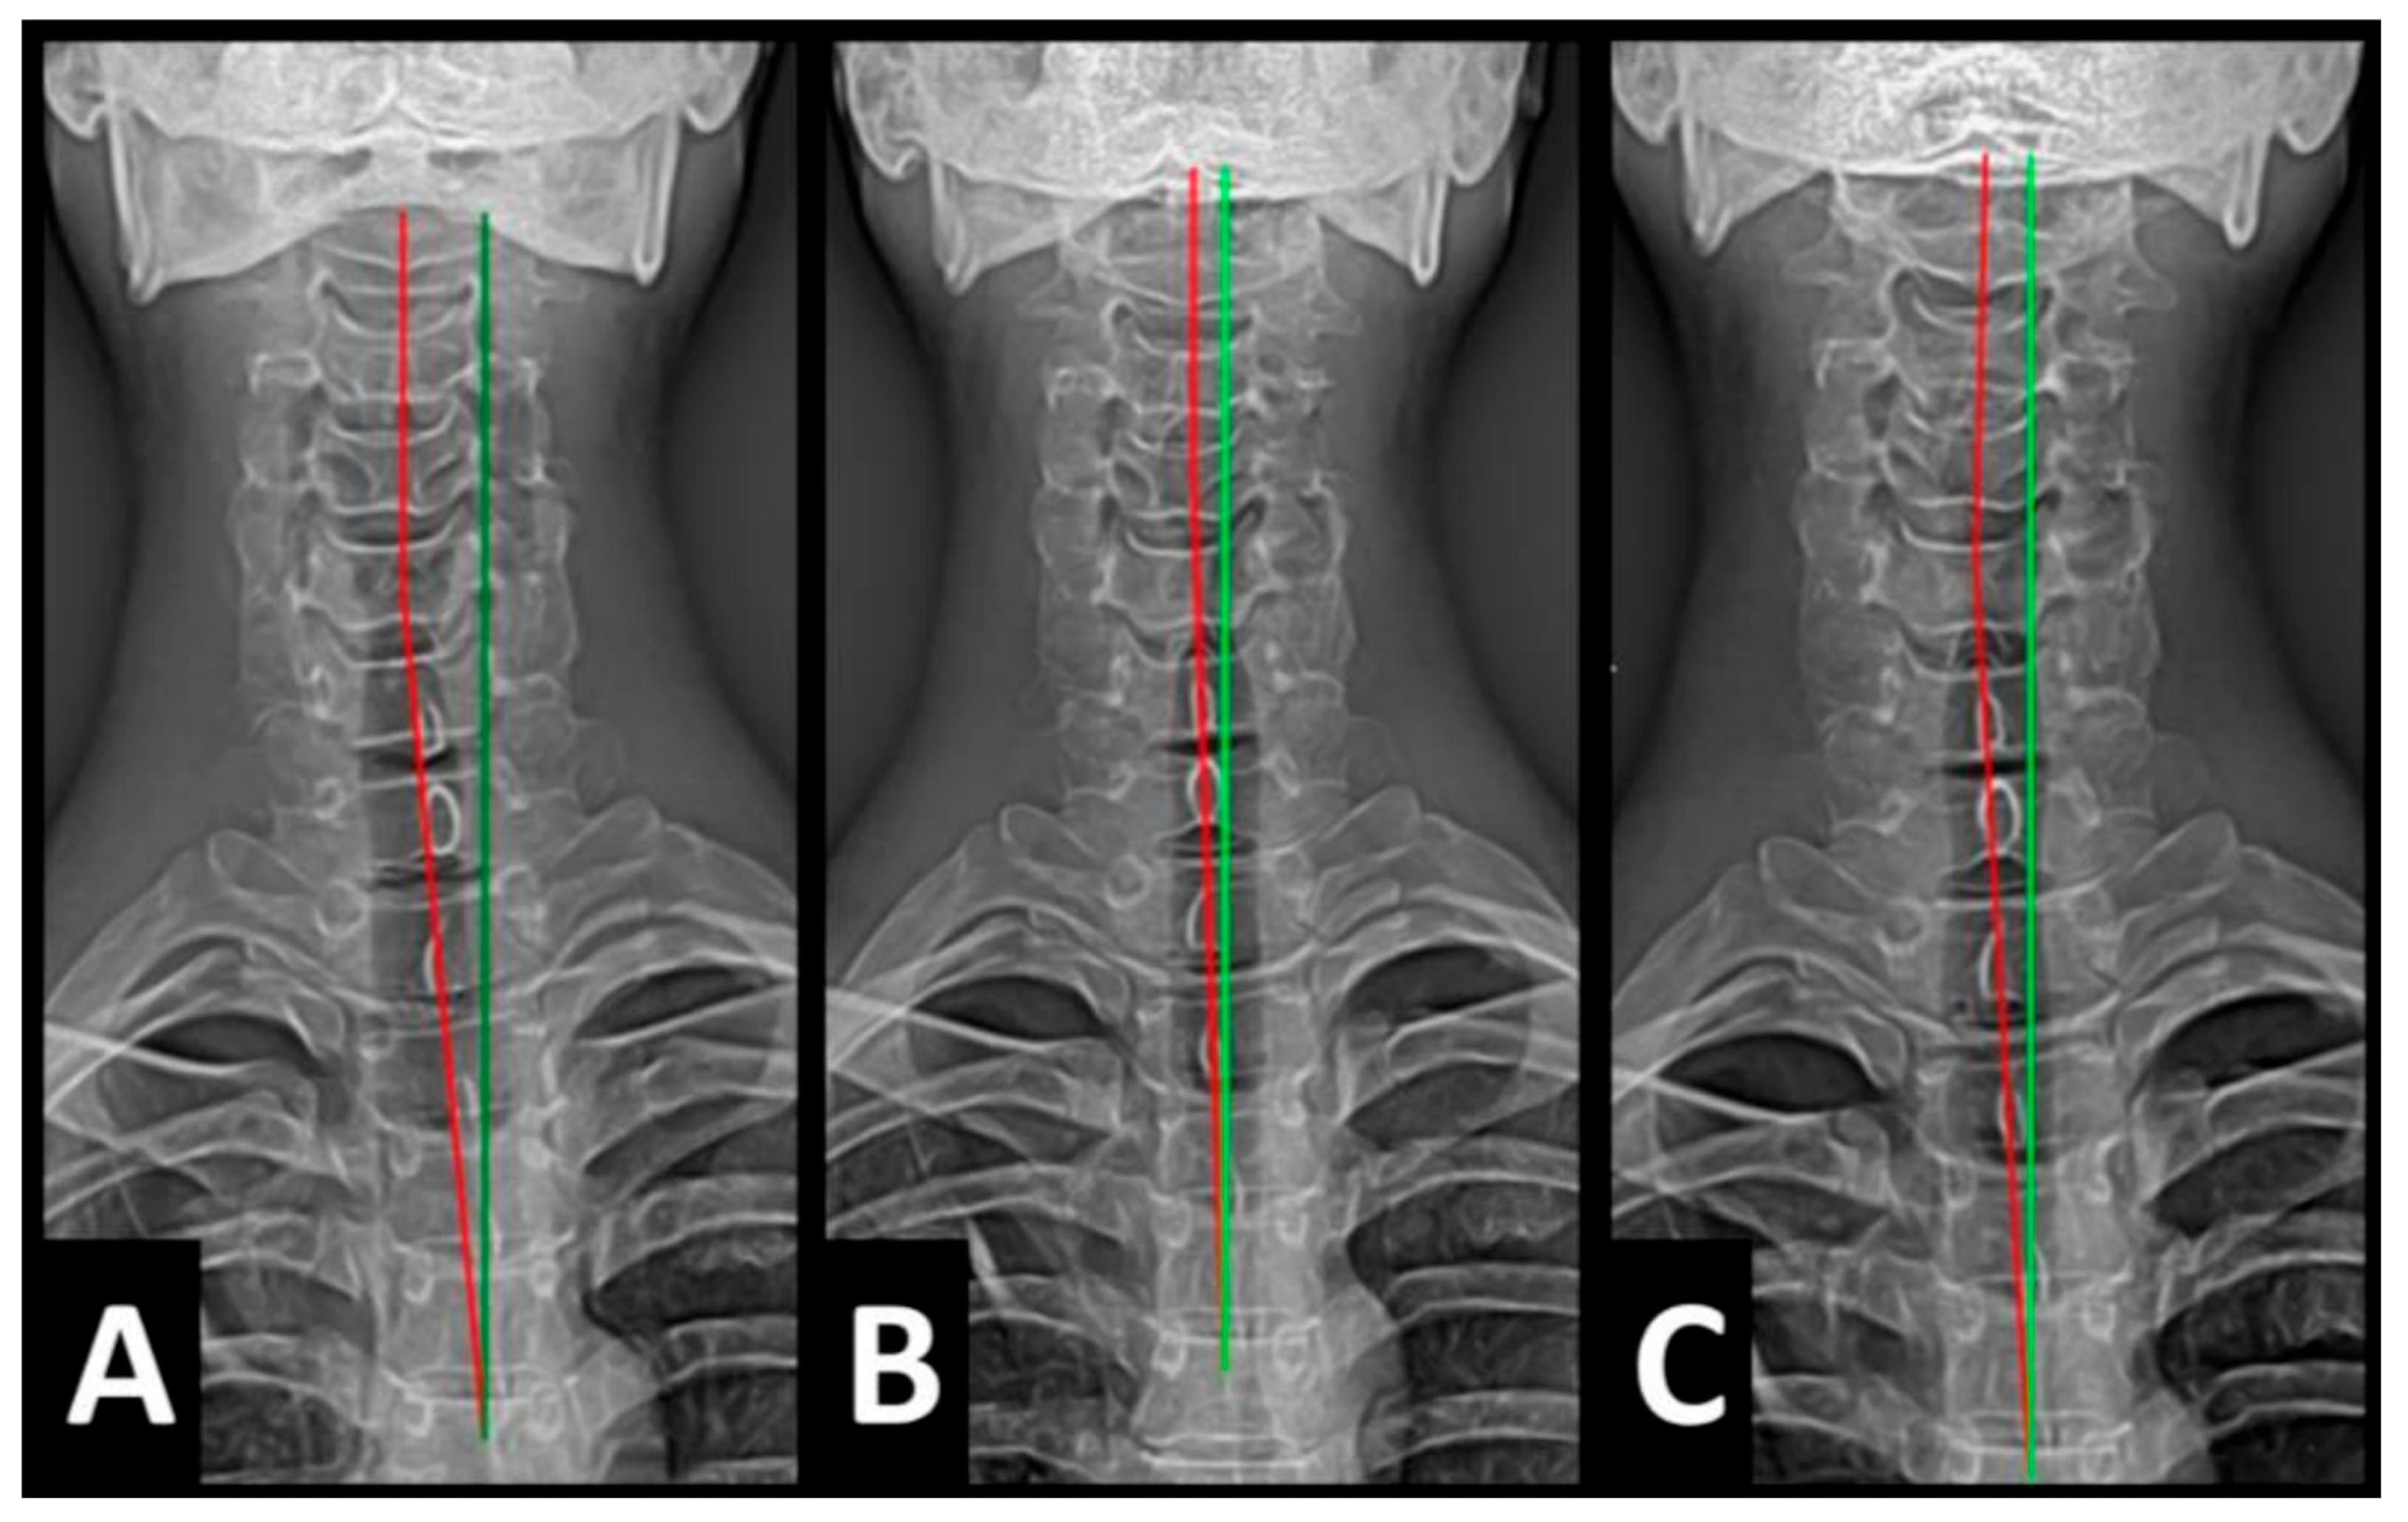

Radiography of the spine was performed with the patient upright in neutral position. Anterior–posterior (AP) and lateral films were assessed using PostureRay® digital radiographic mensuration software (Posture Co, Inc., Trinity, FL, USA) [14]. The program uses the Risser–Ferguson measurement for the AP views and the Harrison posterior tangent method (HPTM) of measurement for the lateral views. The program also compares the patient alignment of both segmental and global measurements to models of ideal spine parameters; prior studies have shown exceptionally high reliability using this system [15]. The sagittal spine absolute rotation angle (ARA) from the 2nd cervical vertebra to the 7th (ARAC2–C7) measured −18.1° (average is −34°, ideal is −42°, pain threshold is −20° [16]) (Figure 2, Figure 3, Figure 4 and Figure 5) and the AP cervical X-ray demonstrated a right lateral flexion angle relative to true vertical of the lower cervical and upper thoracic spine (cervicodorsal angle (CDA)) measuring 5.6° (ideal is 0° [16]) with a right translation of C2 with respect to T5 (TXC2–T5) measuring −17.2 mm (ideal is 0 mm). There was an increased mid-thoracic angle with a right-sided concavity from T1 to T12 (MTAT1–T12) of 9.1° (ideal is 0° [16]) with an increased translation at T8 apex of mid-thoracic angle with respect to T12 (+TXT8–T12) measuring 15.2 mm (ideal is 0 mm). There was a decreased sagittal curvature of the lumbar spine from L1 to L5 (ARAL1–L5) measuring −17.9° (ideal is −40°, average range is 35–45° [16]). The modified Ferguson pelvic radiograph demonstrated a sacral base unleveling in the frontal plane measuring −11.3 mm, being lower on the right. There was a lumbosacral angle from L1 to L5 with an L3 apex (LSA L1–L5) of −84.9° (ideal is 90°).

Post-treatment posture analysis showed improved posture (Figure 1A–C). Post-treatment radiographic examination revealed the following: improved ARAC2–C7 measuring −29.4° (vs. −18.1°); rotation around the z-axis of the thorax (RZT5) measured 1.8° (vs. normal 0°); improved -TxC2–T5 measuring −5.7 mm (vs. −17.2 mm); improved MTA T1–T12 measuring 2.1° (vs. 9.1°); improved +TxT8–T12 measuring 3.5 mm (vs. 15.2 mm); improved ARAL1–L5 measuring −25.1° (vs. −17.9°); improved sacral base unleveling in the frontal plane measuring −1.0 mm low on the left (vs. −11.3 mm low on the right); and improved LSA L1–L5 of −88.0° (vs. −84.9°) (Figure 2B, Figure 3B, Figure 4B and Figure 5B). Post-treatment RODI score was 12% (vs. 54%), indicating minimal disability. All post-treatment SF-36 scores showed improvements (Table 1). One-year follow-up posture analysis showed a maintenance of the improved posture. One-year follow-up radiographic examination revealed maintained sagittal balance and coronal spinal alignment correction improvements (Figure 2C, Figure 3C, Figure 4C and Figure 5C). One-year follow-up RODI score was 2% indicating minimal or resolved disability from baseline (54%). Post-treatment SF-36 scores showed maintained or further improved HRQoL measures reported by the patient. Long term follow-up found minimal forward head posture on the lateral posture photograph, a slight return to baseline on the A-P cervical radiograph with a right head translation measuring 7 mm. Lateral cervical radiograph assessment at long-term found the lordosis to be well maintained at 34° ARA with minimal C2-vertical anterior head translation of 6 mm. lateral lumbar radiograph showed a slight loss of lordosis at follow-up of 19°. All subjective initial symptoms were reported to be resolved at long-term follow-up. Long term follow-up SF-36 scores were the same as post-treatment with the exception of vitality, which was slightly improved (Table 1). There were no positive orthopedic or neurological tests at follow-up. The patient continued to use the ProLordotic neck exerciser at home 1–3 times per week for up to 10 min (Figure 7).

Figure 3. (AC) Pre-treatment, post-treatment, and 1-year follow-up AP cervical radiographs. Image Features: The green line represents a normal, ideal frontal cervical spinal alignment. The red line represents the actual frontal cervical alignment of the C1–T5 vertebrae. The right side of the radiographs are the left side of the patient.